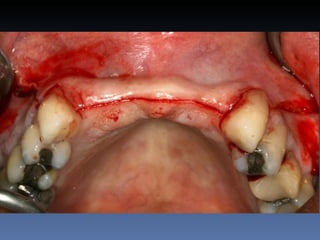

BOX 2

Maria Seemagenn Borges

Idade – 49 anos

Sexo – Feminino

Raça – Caucasiana

ASA – II

Data- 24-04-2012

Diagnóstico: Desdentada

total mandibula

Plano de tratamento: Instalação de 5 implants endo-

ósseos - “Protocolo Branemark”, com carga imediata.